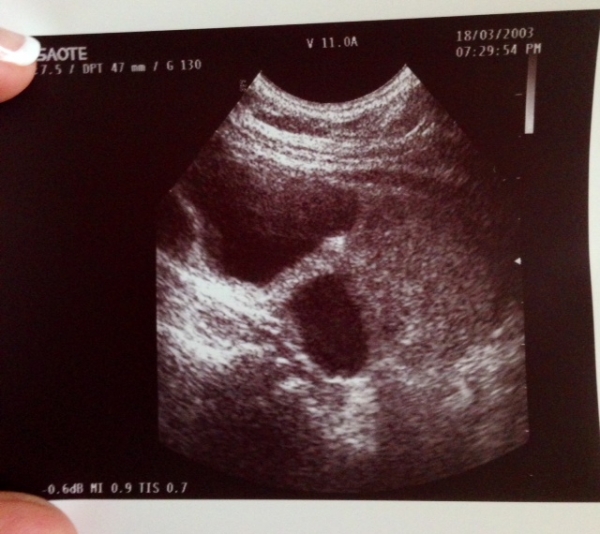

Сегодня нашла вот такое в щитовидке и это не сосуды...неужели кисты такие огромные? пожилая тетенька, жалоб никаких, ранее не обследовалась..

Включала конечно, на доплере тихо.. Самая большая на снимке, в другой доле тоже самое, но поменьше... При этом никаких жалоб

Нужно в двух проекциях снимки делать, а так можно эти образования и за сосуды принять.

Какие размеры этих кист, допплер включали?

Тогда ничего сташного!

Контрольное УЗИ через 3 мес. (если впервые выявлено), консультацию эндокринолога+гормоны щитовидной железы.